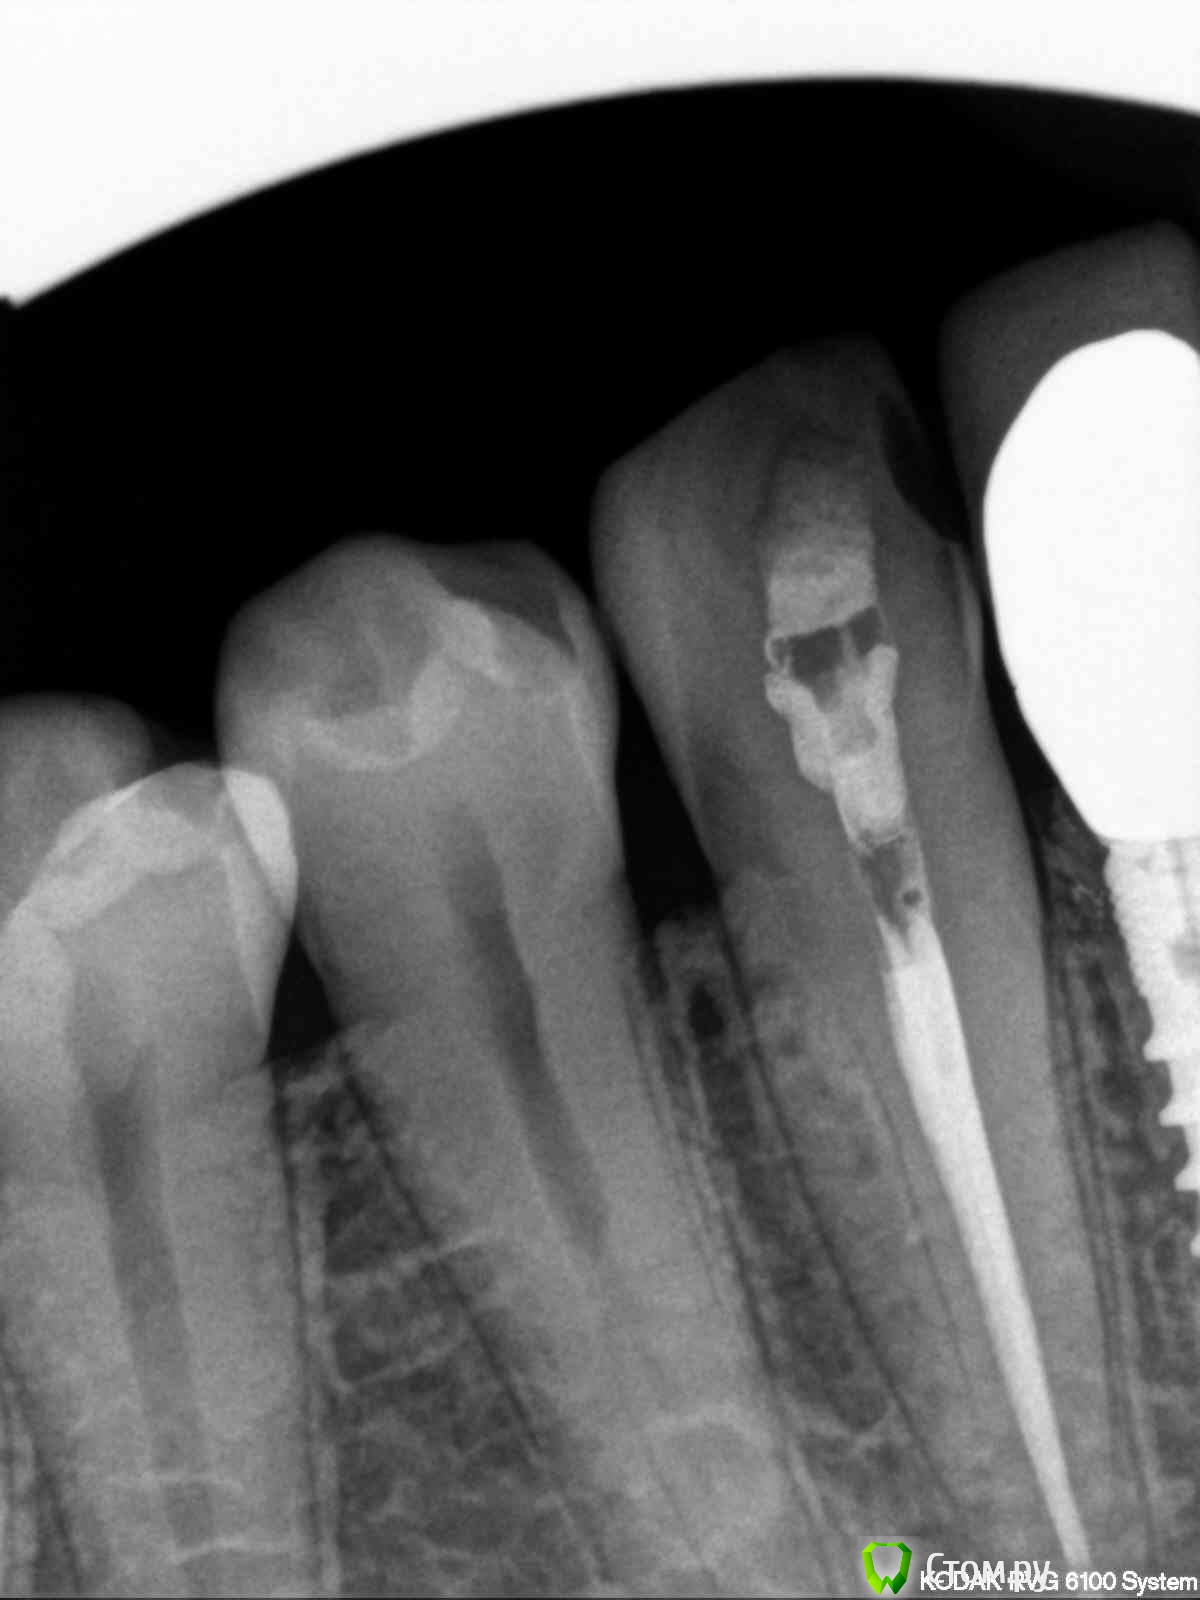

englishlady Опубликовано 30 ноября, 2013 Поделиться Опубликовано 30 ноября, 2013 Уважаемые врачи, проконсультируйте меня, если несложно. Есть 43 депульпированный зуб, он сейчас под временной пломбой. В одном месте на него предложили поставить коронку, в двух клиниках пломбу, поскольку он не сильно разрушен. На еще одном форуме предложили пломбу с стекловолоконным штифтом. Чтобы Вы советовали? Можно ли на него поставить винир. Снимки прилагаю. Заранее спасибо за ответ. Ссылка на комментарий

x3m Опубликовано 30 ноября, 2013 Поделиться Опубликовано 30 ноября, 2013 (изменено) я бы снял старую пломбу (сбоку) или убрал там кариес - по снимку неясно, что там... и посмотрел на общую потерю тканей.Скорее всего, композитом восстановить утраченные ткани (доступ к каналу и, при необходимости - сбоку полость) и покрыть полукоронкой.стекловолоконный штифт абсолютно не нужен. в идеале, надо видеть во рту. или хотя бы фото зуба с язычной стороны и снаружи ...Вы можете сделать фото? Изменено 30 ноября, 2013 пользователем x3m Ссылка на комментарий